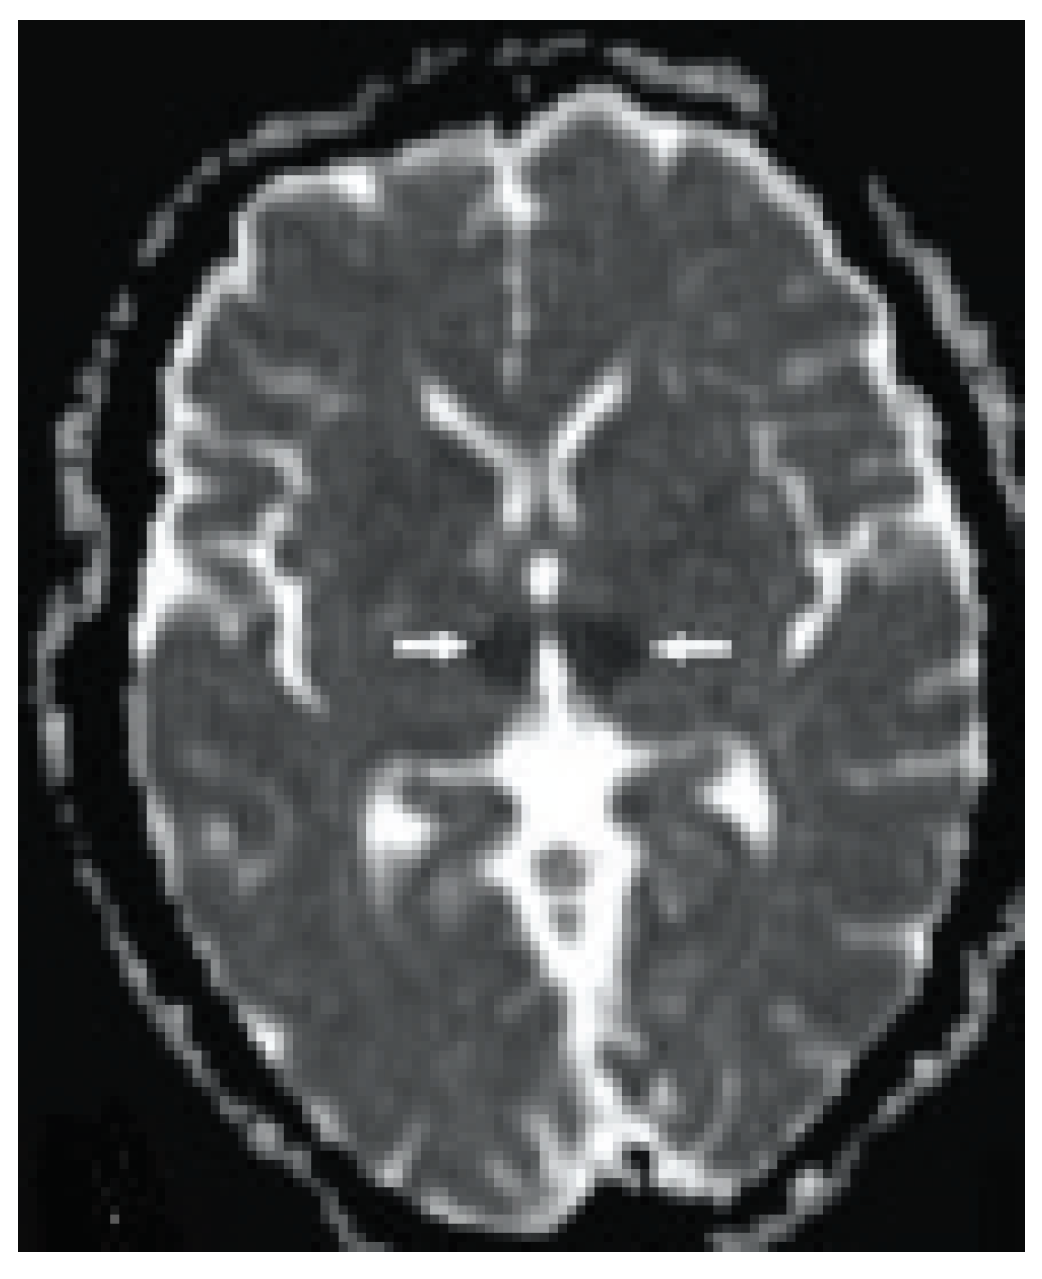

Radiological Investigations: